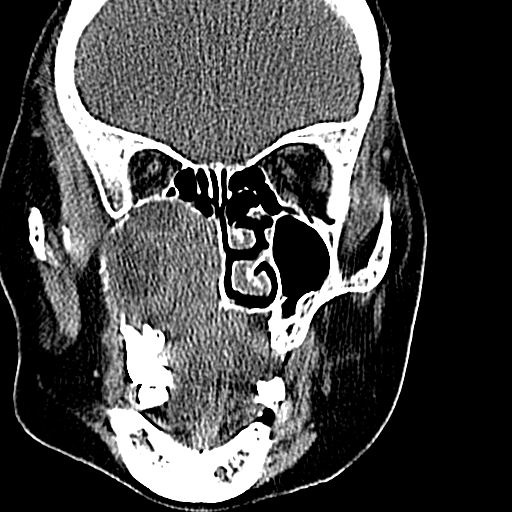

老年患者,女。鼻塞多年。

考虑右侧上颌窦良性占位性病变,粘液囊肿可能性大;建议活检。

膨胀性生长,且骨质无破坏,说明时间久,良性;从密度,边缘看,内部还见坏死区,应该是实性肿瘤,定性,影像学无绝对的特异性

病灶密度很不均匀,骨壁膨胀中有断裂,考虑内翻乳头状瘤可能性大,粘液囊肿不排除

膨胀性生长,且骨质无破坏,说明时间久,良性;从密度,边缘看,内部还见坏死区,应该是实性肿瘤,定性,影像学无绝对的特异性,考虑内翻性乳头状瘤可能